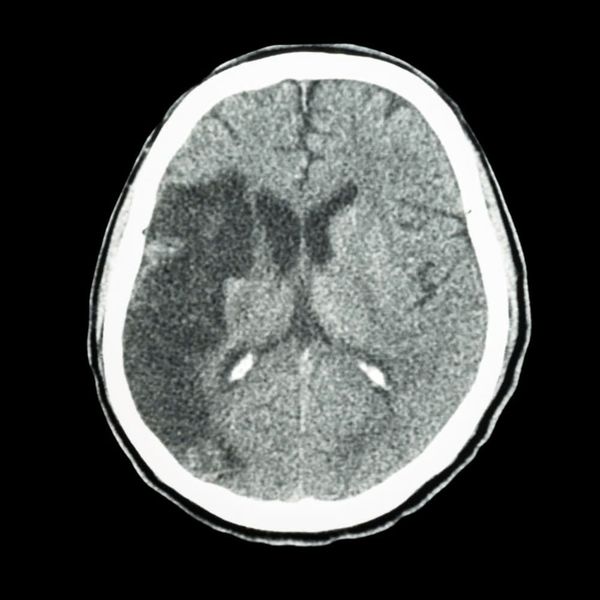

Hình ảnh: CT -scan não một trường hợp đột quỵ do thuyên tắc huyết khối ở người bệnh rung nhĩ